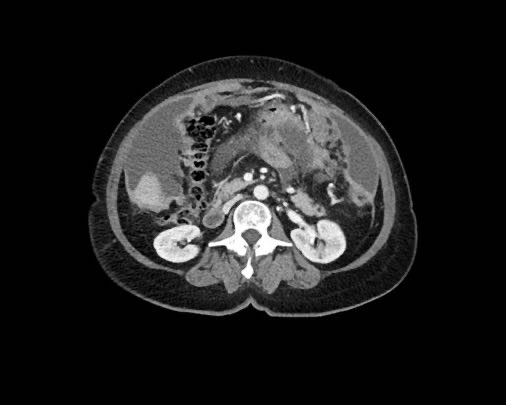

Rãnh cạnh đại tràng

Bất kỳ vị trí nào trong ổ bụng được phủ bởi phúc mạc đều có thể là đích đến của các nốt cấy ghép phúc mạc.

Các vị trí điển hình khác bao gồm rãnh cạnh đại tràng, túi cùng trực tràng-bàng quang hoặc trực tràng-tử cung, dây chằng liềm và mặt bụng của cơ hoành.